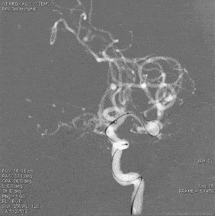

复查标准正侧位造影,右侧ICA、MCA、ACA主干及分支良好,动脉瘤栓塞满意。